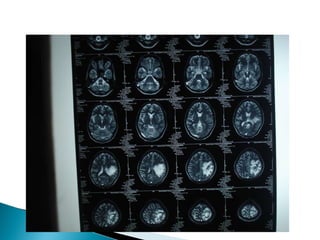

Neurology opinion: ?viral enchephalitis and added T.Phenytoin 100 mg 2HS CSF analysis-Normal MRI Brain-Normal  EEG-Seizure activity noted on Lt frontal cortex

Rpt MRI with MRV and MRA  : -T2 flair showing superior sagital sinus thrombosis. Pt. was started on T.Acitrom 4mg with target INR of 2-3. Pt. was screened for pro coagulant conditions and they are negative(lupus anti coagulant, Protein C & S, anti thrombin III defi. and Sr.Homosysteine).

Combination of non contrast MRI and MRA and MRV : best method for the diagnosis and follow up of CVT . MRI/V  -Early: absence of flow void & isointense on  T1 for occluded vessel;  Hypo intense on T2 Late: hyper intense thrombus on T1 & T2

Combination of noncontrast MRI and MRA and MRV : best method for the diagnosis and follow up of CVT . MRI/V -Early: absence of flow void & isointense on T1 for occluded vessel; Hypo intense on T2 Late: hyper intense thrombus on T1 & T2